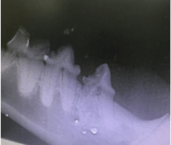

Dr Nicole discovered the RL when she was performing a thorough examination and probing all his teeth. Even under general anaesthesia there can be a painful reaction when RL’s are touched. Dr Nicole took an x-ray of the tooth and it showed the crown of the tooth disappearing. In the photo here we see black where it should be white.